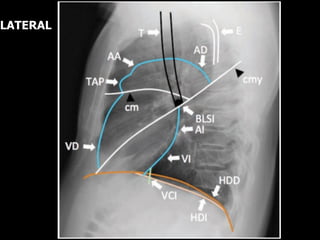

LATERAL

Borde

del VD Borde de AI

VCI

Incremento

de la

radio-

lucidez

Borde del VI

Regiones en la

proyección lateral

¿Qué debe ver?

Espacio

claro

retroesternal

Radiolucidez entre el

esternón y aorta ascendente

Región Hiliar Ausencia de ‘masas’

Cisuras Cisura mayor y menor

delgadas (si son

visibles)

Columna torácica Cuerpos vertebrales

rectangulares, paralelos con

platillos, espacios discales

que mantiene altura.

Diafragma y

surco

costofrénico

posterior (SCP)

Hemidiafragma derecho

discretamente mas elevado

que el izquierdo, SCP

agudo.

retroesternal NL

Ocupación

del espacio

- Linfoma

AP izq

Bronquio

izquierdo

Tronco

de AP

Masa hiliar -

Linfadenopatía

Líq. en

cisuras

mayores

Borramiento del

surco costofrénico

derecho

SCP der

SCP izq

Hemi-

diafragma

der